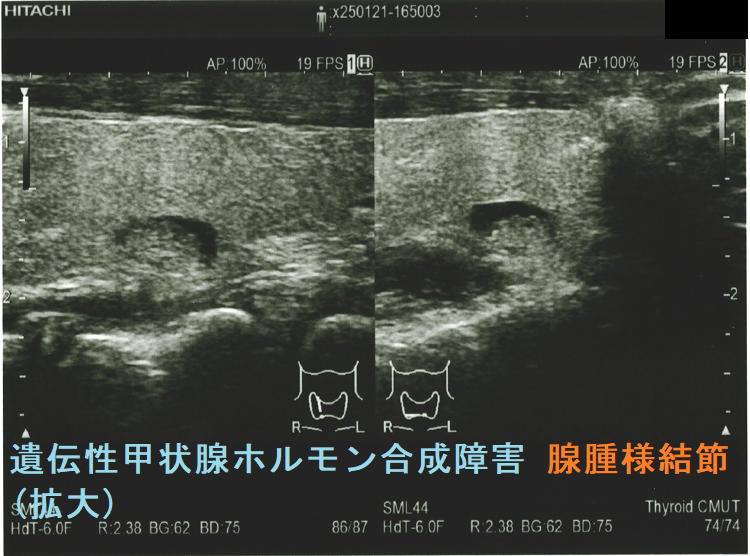

ケース④

遺伝性甲状腺ホルモン合成障害で、サイログロブリン異常症(サイログロブリン遺伝子異常症)以外は、血中サイログロブリンが上昇するにも関わらず、甲状腺自体の破壊性変化に乏しく、マシュマロ様の軟らかい腺腫様甲状腺腫の形態を取る事があります。

遺伝性甲状腺ホルモン合成障害の超音波(エコー)画像は色々なパターンがあります。

- 常染色体優性遺伝型;腺腫様甲状腺腫の形態になります。